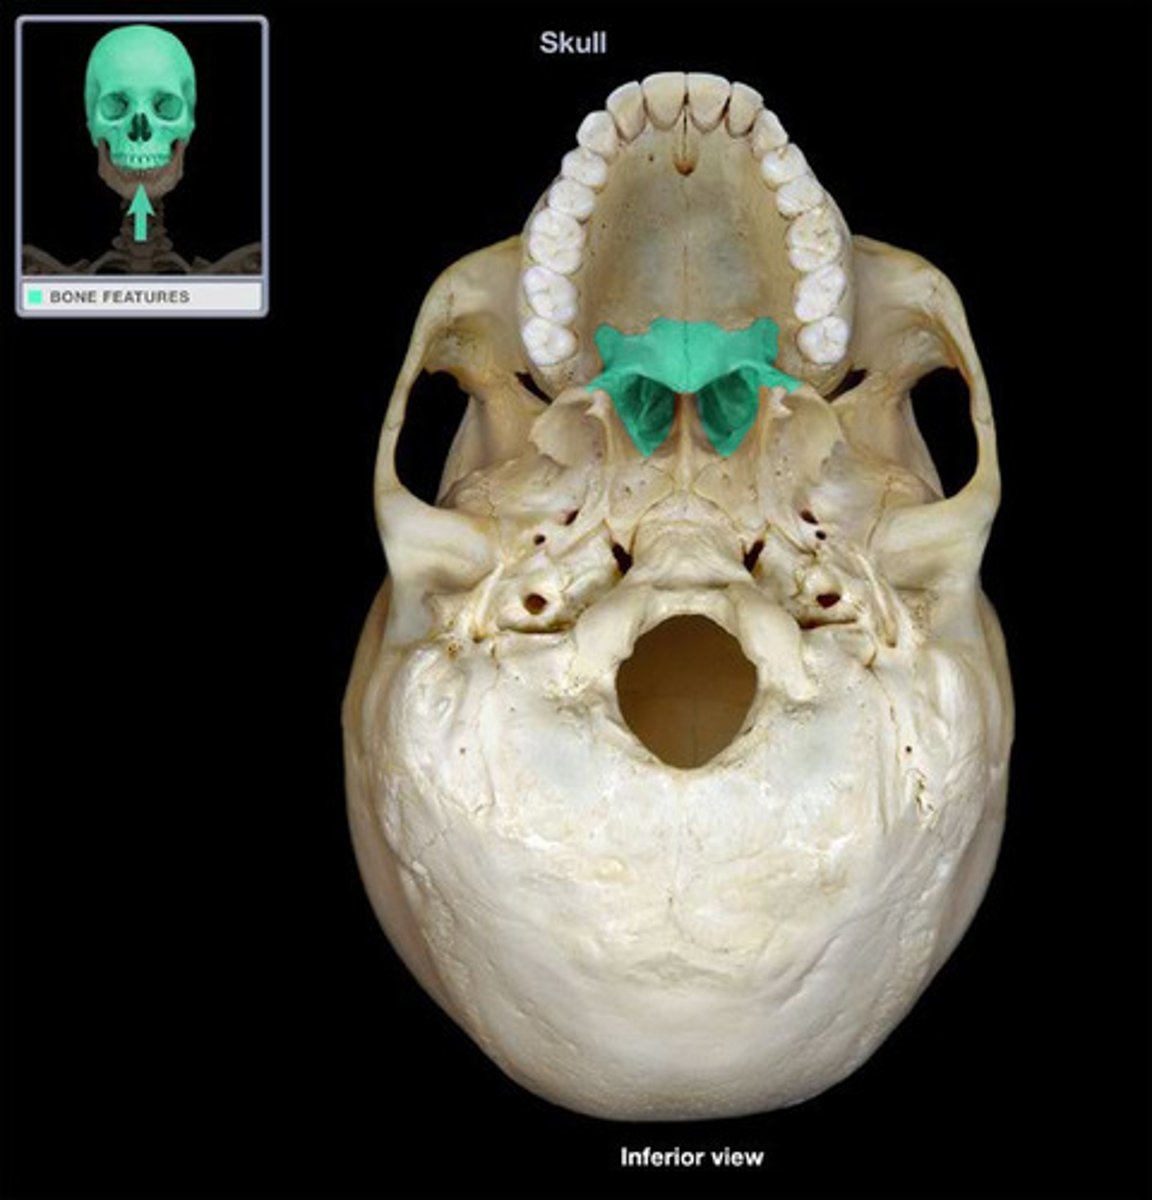

Palantine Bone